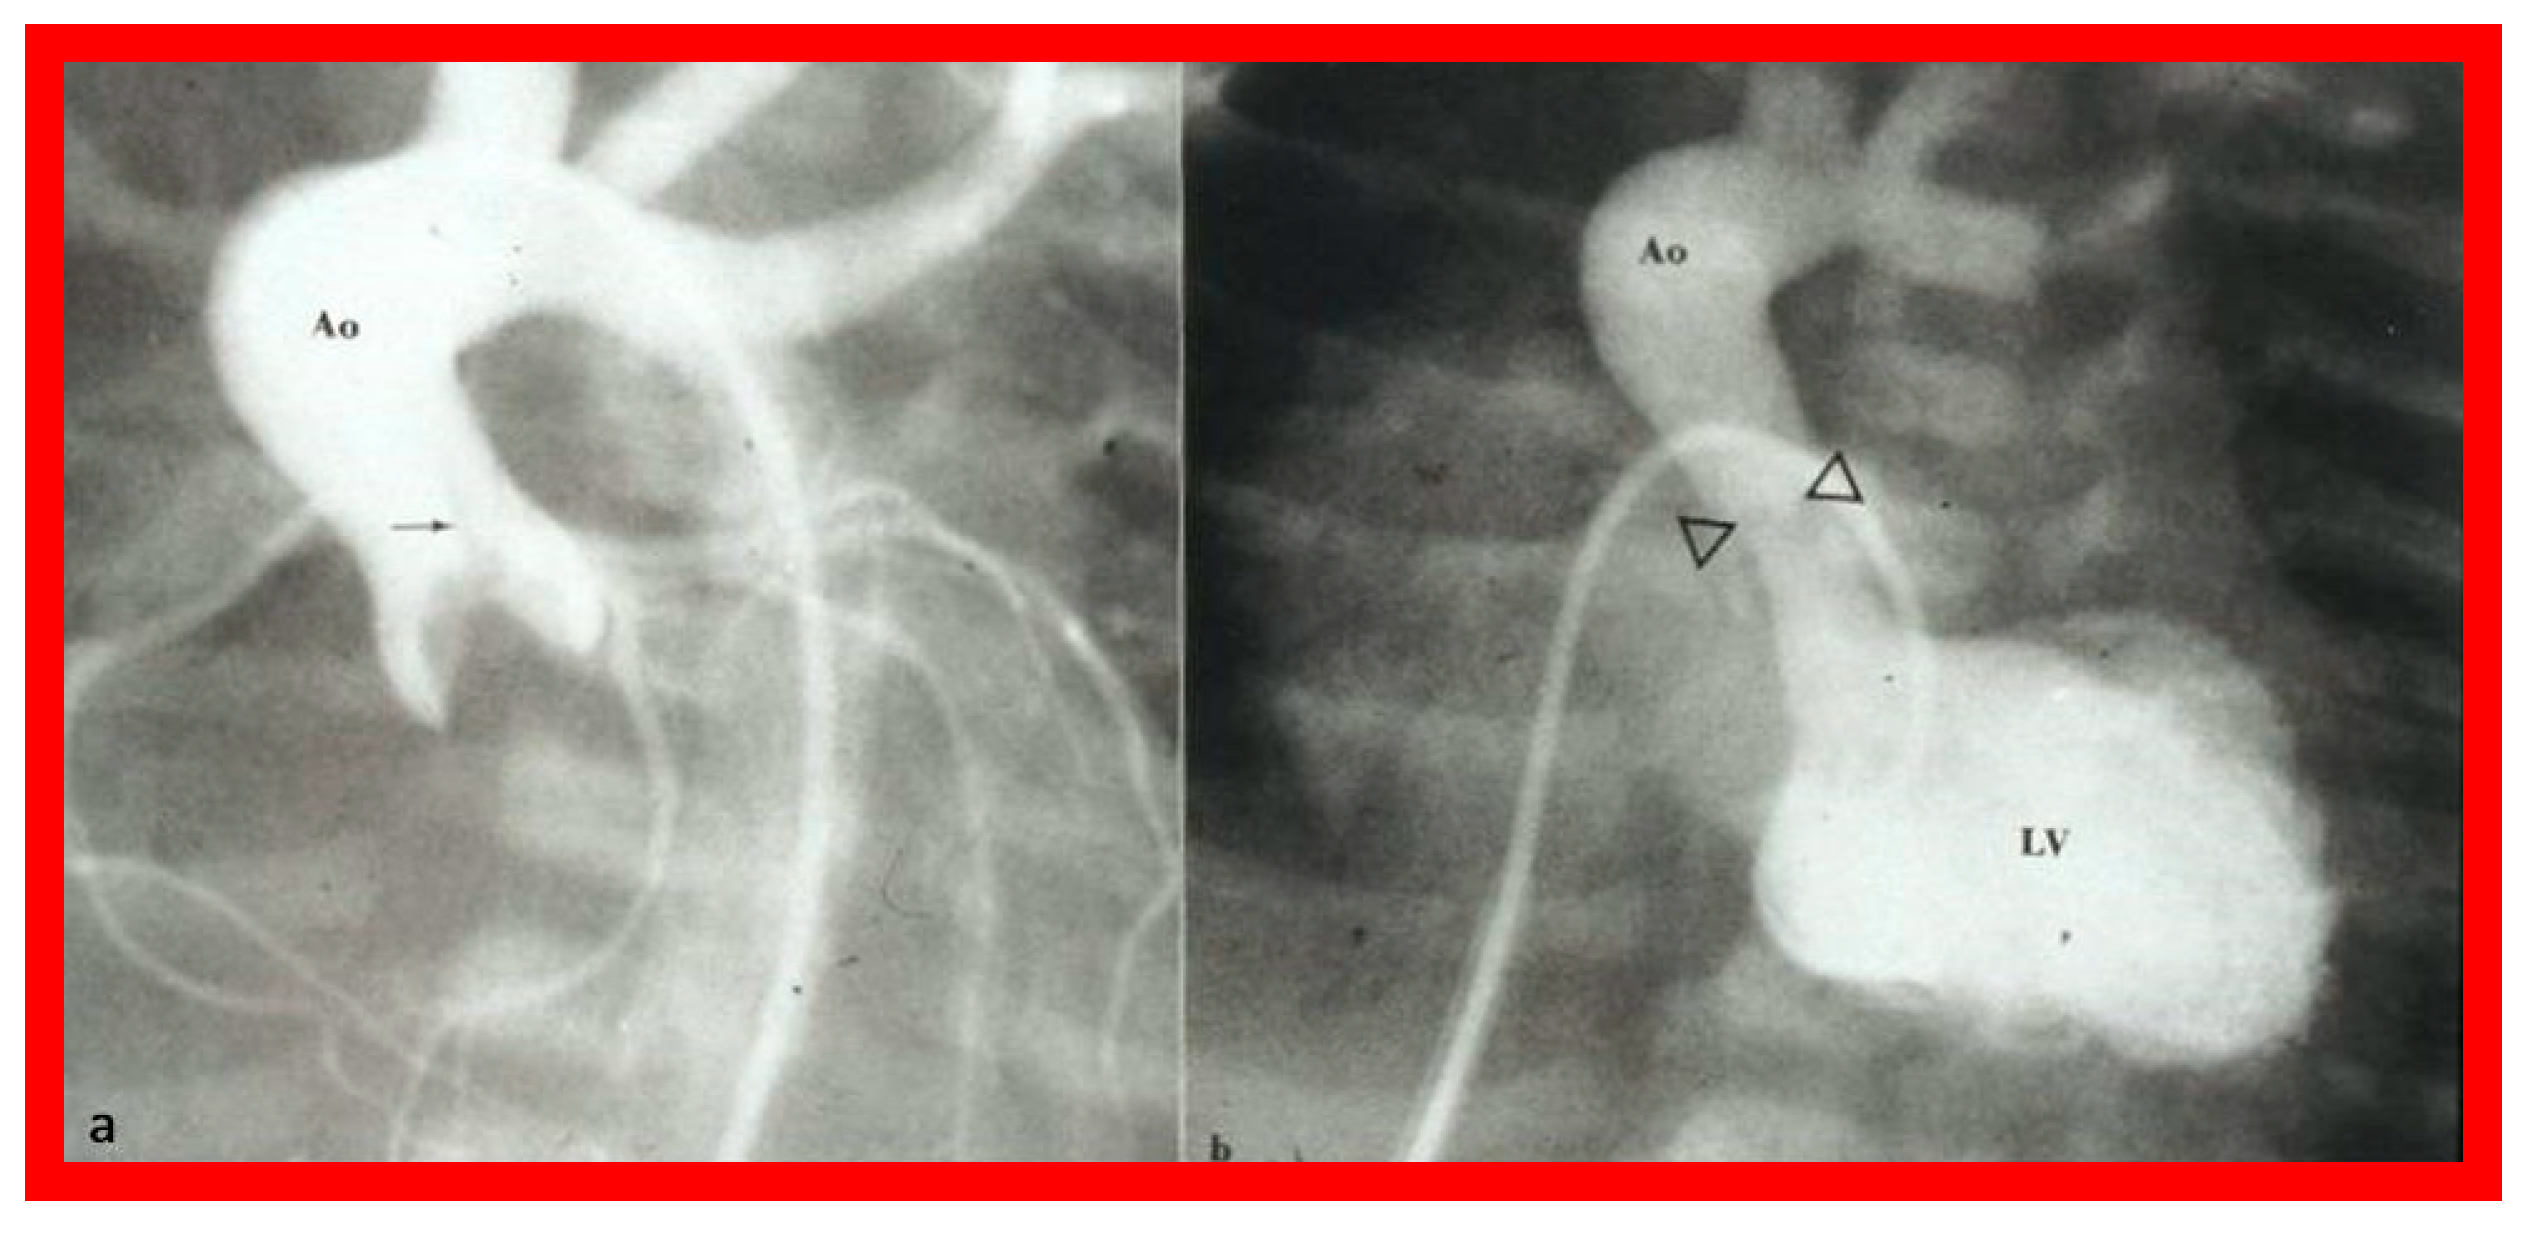

The author made it a practice to urge the neonatologists to insert an umbilical venous (UV) catheter once a cardiac baby is detected and place the tip of the UV catheter in the right atrium before the anticipated closure of the ductus venosus. During BAV procedure, the UV catheter is switched over a guidewire with a 5-F sheath with the tip of the sheath placed in the low right atrium [55,56,57]. Standard hemodynamic data are recorded, aortogram (Figure 26a) and/or left ventricular (LV) cine-angiogram secured, and the diameter of the aortic valve annulus is measured in multiple projections. Such data supplements echo-measured valve annulus diameter.

The balloon valvuloplasty catheter is switched over to a #4-F multipurpose catheter and the guidewire is withdrawn. Pullback pressure recordings across the aortic valve are documented and aortic root angiogram is performed. LV cine-angiogram (Figure 26b) may be performed as deemed suitable. Heparin is given at the start of the BAV and activated clotting times (ACTs) checked. Vancomycin is administered for prophylaxis because of extensive manipulation of the umbilical region during the BAV [55,56,57].

Figure 26. a. Selected frame from the ascending aorta (Ao) cine-angiogram prior to balloon aortic valvuloplasty showing a domed aortic valve and a very narrow jet (arrow) of un-opacified blood from the left ventricle (LV) to the Ao. Post-stenotic dilatation of the Ao is also seen. b. LV cine-angiographic frame following balloon valvuloplasty demonstrating dilated LV and wide jet of contrast material (arrowheads) across the aortic valve. Reproduced from Reference [56].